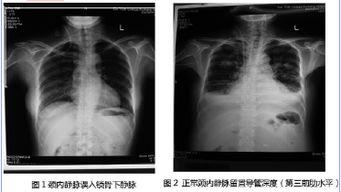

你有没有想过,在医院里,医生们是如何给病人做颈内静脉...